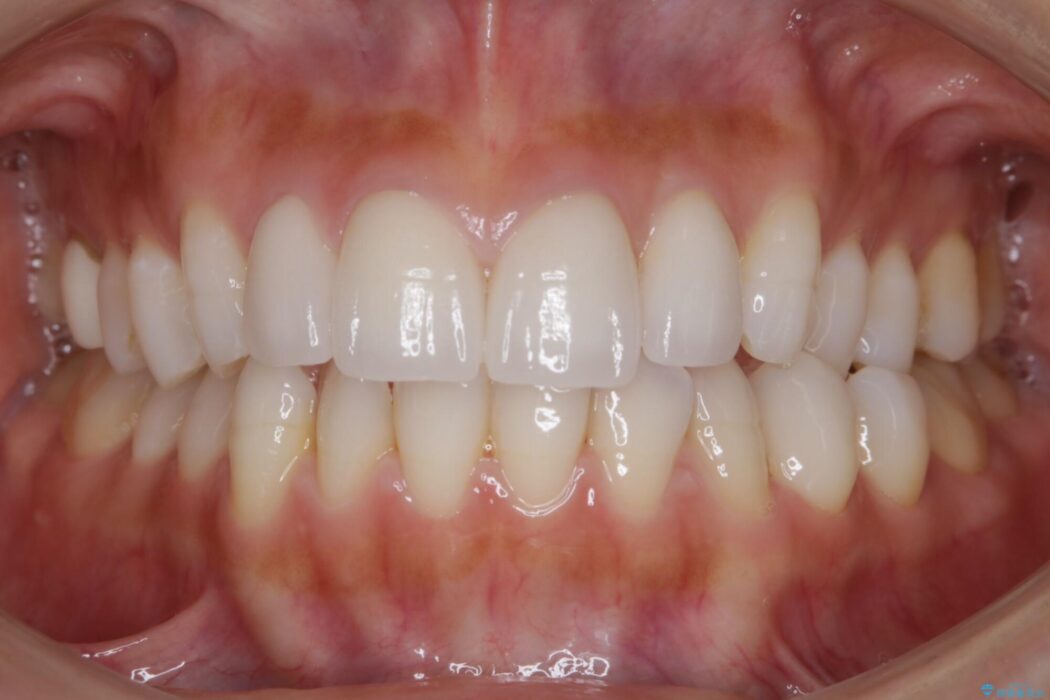

既定のインビザラインの装着時間を守っていただけたこともあり整ったアーチとなりました。

特に気にされていた噛み合わせは改善されご満足いただけました。